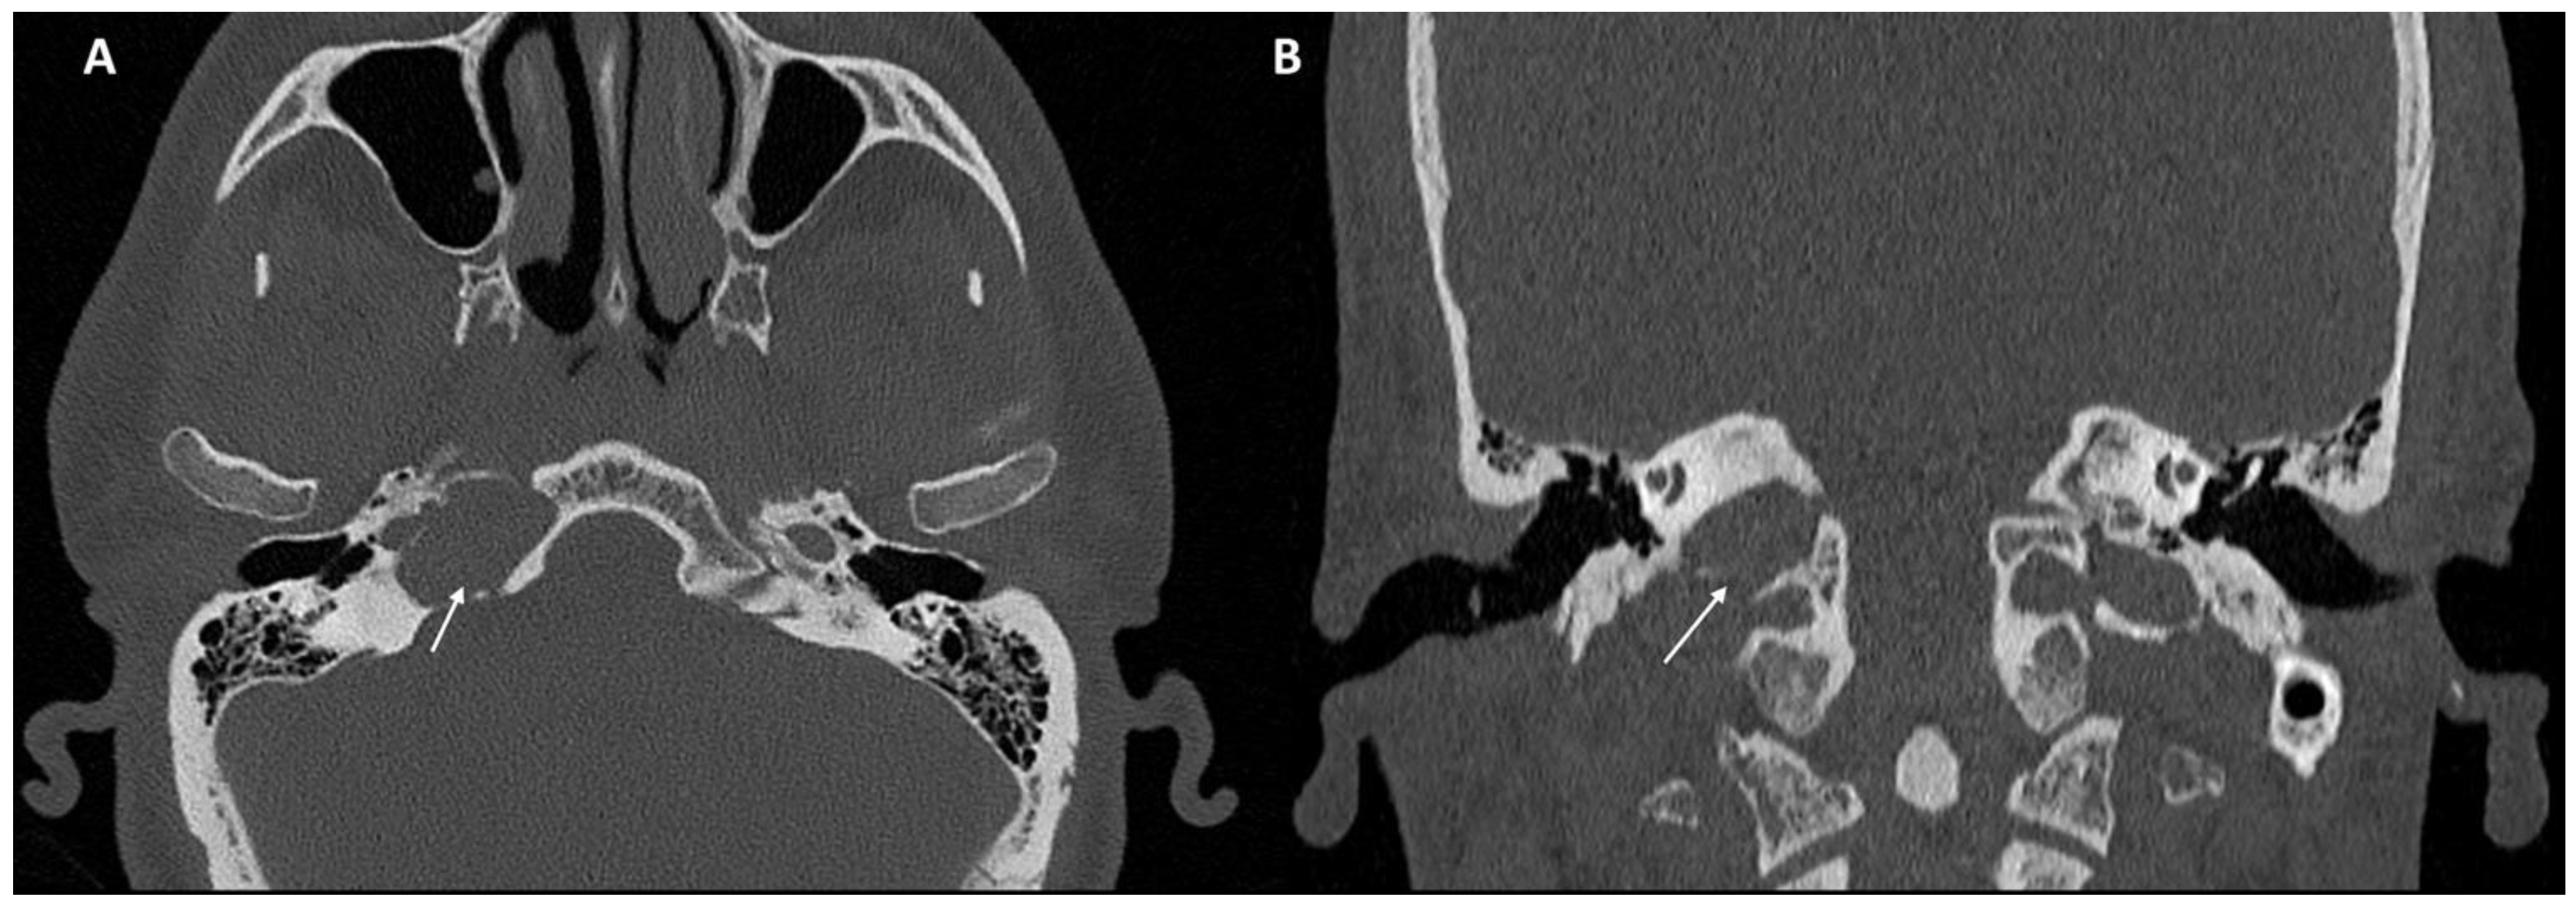

Imaging data from each patient were examined by an expert radiologist and an ENT specialist focusing attention not only on the location of the cyst, but also on the adjacent structures involved. Considering the available literature on symptoms and hypothesized regions of radiological involvement, we established a reproduceable pre-operative radiologic map to better correlate typical symptoms, such as headache, hearing loss, vestibular symptoms, tinnitus, otitis media, diplopia, and facial paresthesia, with PACG. The following regions were considered: (1) temporal lobe/posterior fossa compression (Figure 1); (2) Meckel’s cave compression (Figure 1); (3) Eustachian tube compression/erosion (Figure 2); (4) internal auditory canal erosion (Figure 3); (5) cochlear basal turn erosion (Figure 4); (6) Dorello canal involvement (Figure 5); (7) jugular tubercle erosion. The latter parameter was introduced to evaluate its possible correlation with an atypical clinical presentation, namely fainting. To standardize all these radiological examinations, the jugular tubercle was defined in axial sections as the bony convexity medial to the jugular foramen just above the hypoglossal canal; in coronal sections, it is the bony part directly above the hypoglossal canal (Figure 6).

Figure 6. CT scan in the axial (A) and coronal (B) planes of the jugular tubercle (white arrow) defined as the bony convexity medial to the jugular foramen just above the hypoglossal canal (in axial sections) or the bony part just above the hypoglossal canal (in coronal sections).